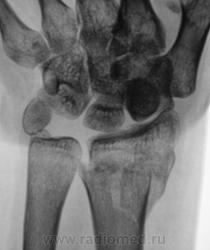

Травма.   Пациент направлен на рентгенографию лучезапястного сустава.

Вывих трапеции и гороховидной костей, ну и перелом "луча" в т.м., куда же без него.